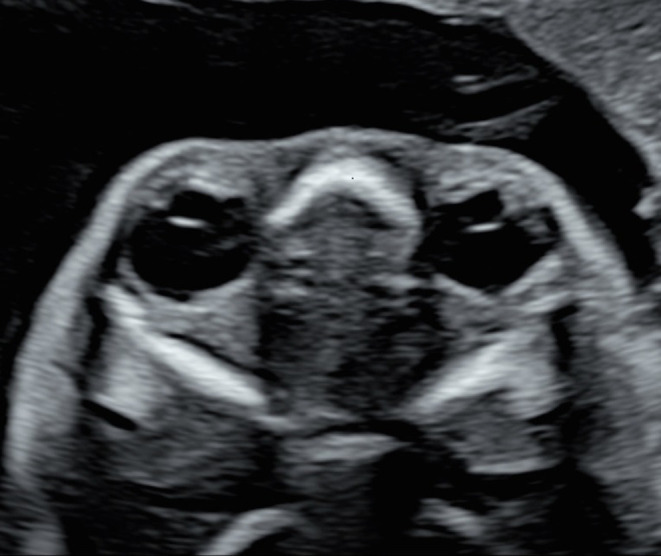

Results: Among the 29 cases, 18 (62.1%) showed complete hyperechogenicity of the lens (type I), 6 (20.7%) showed dot or cluster hyperechogenicity within the lens (type II), and 5 (17.2%) showed the "double-ring" sign (type III). Moreover 18 (62.1%) involved isolated cataract and 11 (37.9%) involved cataract associated with extraocular abnormalities, with central nervous system and cardiac abnormalities being the most common. In terms of potential etiology, five cases (17.2%) had a family history, and genetic testing was performed in eight cases, with five of them showing abnormalities. Cases 2 and 16 involved two fetuses of the same pregnant woman, both of which had a hemizygous mutation of the OCRL gene (c.1514G > A). Moreover Case 3 involved Trisomy 13, and Case 17 had heterozygous mutations of the RAB3GAP1 gene (c.718C > T and c.1879dupA). Furthermore, Case 21 had a heterozygous mutation of the NHS gene (c.375C > A). Among the 29 cases, pregnancy was terminated in 21 (72.4%) and was continued in 4 (13.8%).

Conclusion: Congenital cataract, defined as lens opacity, presents as complete hyperechogenicity of the lens, a double-ring sign, or dot and cluster hyperechogenicity within the lens on prenatal ultrasound. Prenatal ultrasound can help assess the eyes and other systems during prenatal or postnatal examinations and can provide additional information for prenatal counseling and early postnatal treatment of congenital cataract.